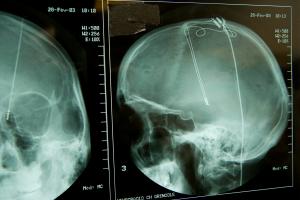

PARKINSON : Les avantage d’une stimulation profonde mais auto-ajustable

Actualité publiée le 02/09/2024PARKINSON : La bactérie du microbiote qui pourrait éliminer la maladie